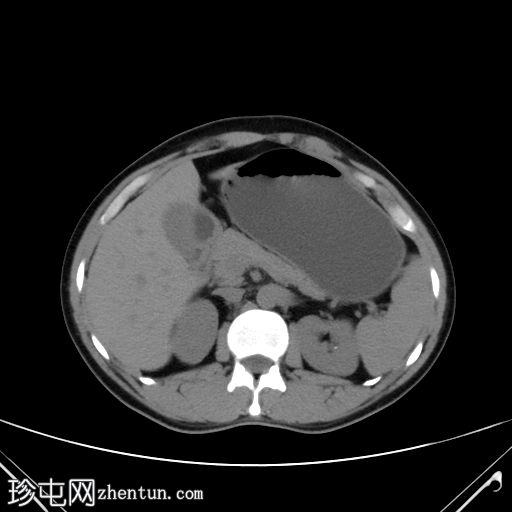

轴位肾脏

延迟期

右肾存在重复肾盂输尿管畸形,输尿管重复;但输尿管远端显影不佳。膀胱内可能存在两个位置接近的输尿管开口。

可见一局灶性息肉样腔内病变,起源于右侧膀胱输尿管连接处外侧的后外侧壁,增强后轻度强化。

双肾均可见小结石。

双肾未见肾积水。